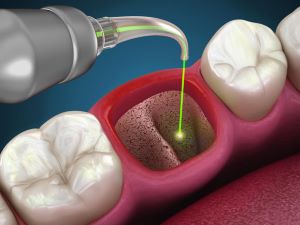

We provide a full range of services for both adults and children, everything from braces and clear aligners to dental implants, root canal treatment, wisdom tooth removal, whitening, and more. Whatever your smile needs, we’ve got you covered!

Most people come to us for our clear aligner expertise (we’re an Angel Aligner KOL clinic!), self-ligating metal braces, dental implants with soft tissue management, and early orthodontic care for kids. These are our signature services that many patients recommend us for.